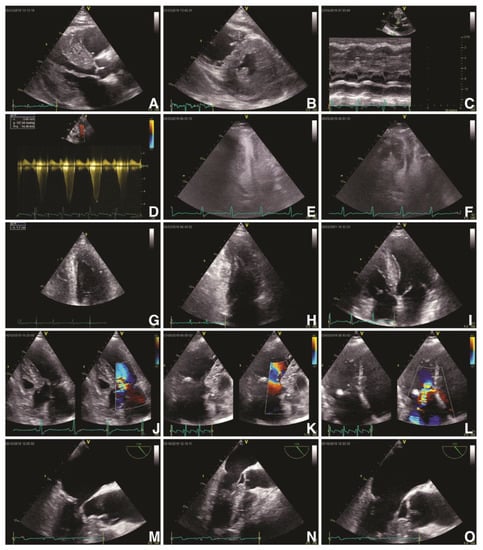

On the other hand, advanced multimodal imaging plays a paramount role in diagnosing and risk stratifying of these patients, especially by the joint use of echocardiography and cardiac magnetic resonance imaging (CMR) [27]. Both European Society of Cardiology (ESC) and American Heart Association/American College of Cardiology (AHA/ACC) guidelines recommend standard transthoracic echocardiography (Figure 1) as the first-encounter imaging tool in patients suspected of HCM because it can provide a significant overview about LV hypertrophy, LV systolic and diastolic function, LVOT or intraventricular dynamic obstruction and mitral valve phenotypic particularities [28,29,30]. Echocardiographic findings in patients with HCM are described in Table 1 [27,28,31].

Figure 1. Echocardiographic findings in hypertrophic cardiomyopathy. TTE: obstructive HCM (Maron type III) in PLAX (A) and PSAX (B) views with an IVS of 23 mm and a ILW of 19 mm, with SAM of MV’s anterior leaflet in PLAX M-Mode (C) and a LVOT gradient of 127 mmHg and velocity of 5.65 m/s (D); contrast transthoracic echocardiography of a HCM with mid-cavity obstruction and apical LV aneurysm in A4C in systole (E) and diastole (F); HCM (Maron type IV) with isolated hypertrophy (18 mm) of the apical segment of LV’s lateral wall (G, H); non-obstructive HCM (Maron type II) with isolated hypertrophy of the IVS (20 mm) (I); obstructive HCM with SAM of the MV’s anterior leaflet and of its chordae tendineae with leads to severe MR (JL). TEE: obstructive HCM with SAM of MV’s anterior leaflet—A2 scallop (MO). Abbreviations: A4C, apical four-chamber view; HCM, hypertrophic cardiomyopathy; IVS, interventricular septum; LV, left ventricle; LVOT, left ventricle outflow tract; MV, mitral valve; PLAX, parasternal long-axis view; PSAX, parasternal short-axis view; SAM, systolic anterior movement; TEE, transoesophageal echocardiography; TTE, transthoracic echocardiography.